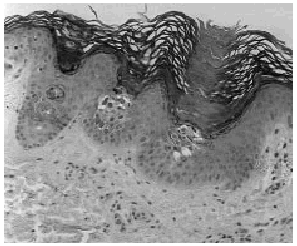

Mujer de 52 años, con antecedentes de accidente cerebrovascular sufrido hacía 10 años, que consultó por presentar desde hacía más de 2 años áreas hiperpigmentadas y pruriginosas en el tercio superior de la espalda. Con la sospecha clínica de amiloidosis maculosa se realizó una biopsia cutánea. En ella se observó una hiperpigmentación de la capa basal y la presencia en las pápilas dérmicas de un material rosado de aspecto cuarteado característico de la amiloidosis maculosa (Fig. 1) junto a cambios focales de hiperqueratosis epidermolítica (Fig. 2). Las tinticiones con Rojo-Congo y citoqueratinas de alto peso molecular fueron negativas.

FIG. 2.--Presencia de dos mínimos focos de hiperqueratosis epidermolítica en el seno de la amiloidosis maculosa.

La hiperqueratosis epidermolítica es un término descriptivo empleado para referirse a unas características histológicas bien definidas: hiperqueratosis compacta, vacuolización perinuclear del estrato granuloso y de la porción superior de la capa espinosa junto a gránulos de queratohialina de morfología irregular (2-4). Constituye un patrón histopatológico de la epidermis que puede evidenciarse en una amplia variedad de alteraciones cutáneas; desde dermatosis congénitas, como la EICA, algunos nevos epidérmicos o la queratodermia palmo-plantar hereditaria tipo Voerner, hasta procesos adquiridos como el acantoma epidermolítico solitario, el acantoma epidermolítico diseminado o la hiperqueratosis epidermolítica actínica persistente (5). Además, la hiperqueratosis epidermolítica puede ser un hallazgo casual en bipsias tomadas para estudiar otras enfermedades cutáneas. Esta hiperqueratosis epidermolítica «incidental» puede aparecer, por ejemplo, en quistes epidérmicos, queratosis seborreicas, carcinomas espinocelulares, carcinomas basocelulares, queratosis actínicas, nevos melanocíticos, melanomas, dermatofibromas, granuloma anular, dermatitis numular, mucosa normal y liquen amiloideo (2) entre otras dermatosis inflamatorias y tumorales (6). Aunque es bien conocido que una mutación en los genes que codifican las K1 y K10 determina la hiperqueratosis epidermolítica en la EICA, la etiopatogenia de la hiperqueratosis epidermolítica incidental continúa sin aclararse (2, 3, 5).